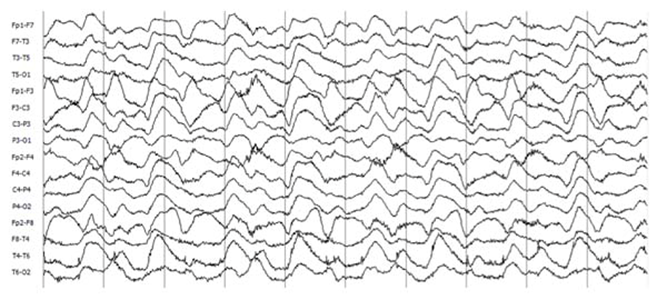

El electroencefalograma (EEG) es anormal en la mayoría de los pacientes (en 85 a 90 %); no obstante, sus hallazgos suelen ser inespecíficos (actividad lenta y desorganizada). En algunos casos, los registros pueden mostrar actividad epiléptica focal o generalizada.2 Treinta por ciento de los pacientes con encefalitis anti-NMDAr presenta un patrón conocido como delta brush extremo (extreme delta brush), asociado a cuadros clínicos más graves y prolongados55,56 (Figura 3).

Figura 3 EEG con patrón extreme delta brush. Montaje bipolar longitudinal doble banana, filtro de baja 1Hz (0.3 CT), filtro de alta 50Hz, filtro de Notch 60Hz. Sensibilidad en 7μV/mm. El estudio pertenece a una mujer de 16 años con cuadro grave de encefalitis anti-NMDAr.